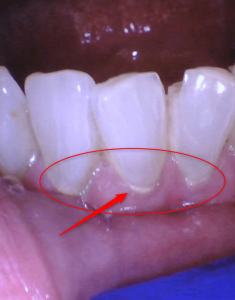

Teeth cleaning: BEFORE AND AFTER

Examine the photos below show teeth before and after cleaning by the hygienist. This tartar buildup was just two months since the cleaning. However, this patient is very prone to tartar buildup. The average person may take many more months to accumulate this amount of tartar. However, a dental hygienist can diagnose your tartar development and prescribe the frequency of having your teeth cleaned.